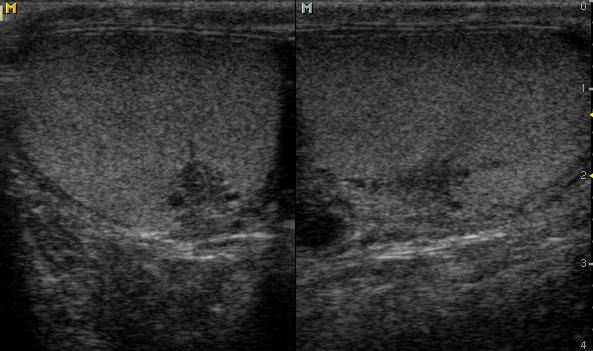

Nang mào tinh (Epididymal cyst)

16/03/2026